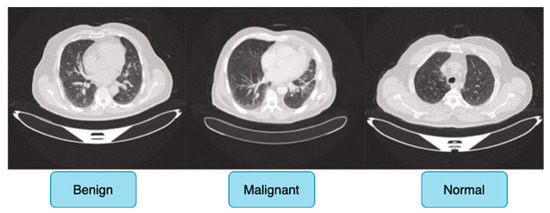

The IQ-OTH/NCCD dataset comprises 1190 CT scan slices from 110 individuals with diverse demographic backgrounds, including age, gender, education level, place of residence, and lifestyle factors, and is categorized into three diagnostic groups: 40 malignant cases, 15 benign cases, and 55 normal (healthy) cases, ensuring a balanced and meaningful distribution for classification tasks.

Figure 6 shows sample images for benign, malignant and normal lung cancer CT images from the dataset.

Originally, the dataset comprised 512 × 512 DICOM CT images; however, to enhance compatibility with deep learning frameworks while preserving medical fidelity, these images were converted to a lossless PNG format. This conversion retains essential radiological features, ensuring the dataset remains suitable for robust feature extraction in deep learning-based cancer detection models. The dataset is publicly accessible via the Kaggle platform, promoting reproducibility and further research advancements [